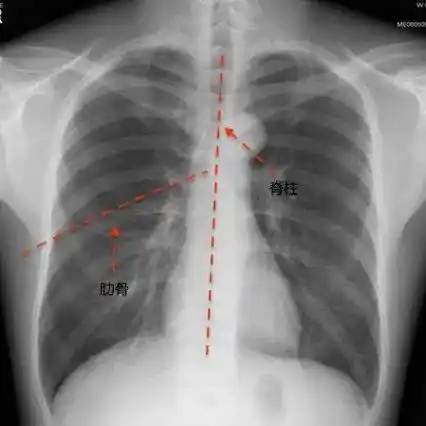

正常的胸廓左右对称,如果出现胸廓左右不对称,鸡胸,漏斗胸及肋骨隆起